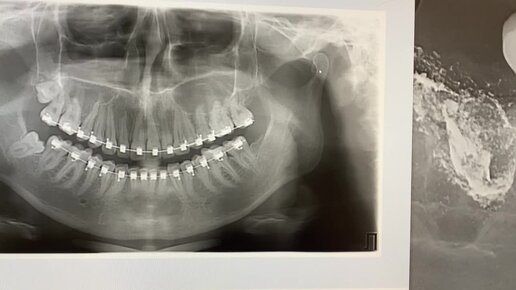

Как удаляют зубы мудрости, которые лежат под наклоном?